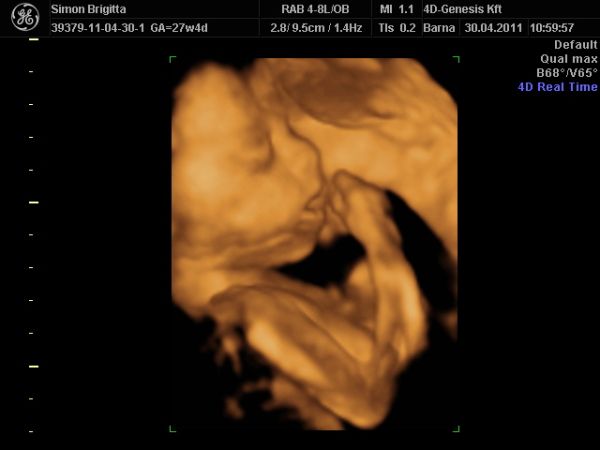

Már nagyon fáradt vagyok, de mindenképpen be akartam jelentkezni, mert ma voltunk a 4D Genesisbe és az étteremben is.

Először természetesen az ultrahangról: annyira szuper volt újra látni a kiscsajt, merthogy még mindig puncis szerencsére :lol:

Most készített a szonográfus 2D-ben néhány igazi "hamburger" fotót!

Teljesen egészséges, fejvégű, mindene rendben van, a méhlepény még mindig mélyen tapad, magzatvíz átlagos, lepény 0. fokban érett.

És legnagyobb meglepetésemre nagyobb a "koránál", a buksija alapján 29+1, az adatok átlaga alapján 28+5 (ténylegesen pedig 27+4).

Becsült súlya 1220 gramm!

Ami a legnagyobb élmény volt nekünk: egy az egyben úgy néz ki, mint Luca a 32. heti 4d-s ultrahangon anno! Hihetetlenül hasonlítanak egymásra!